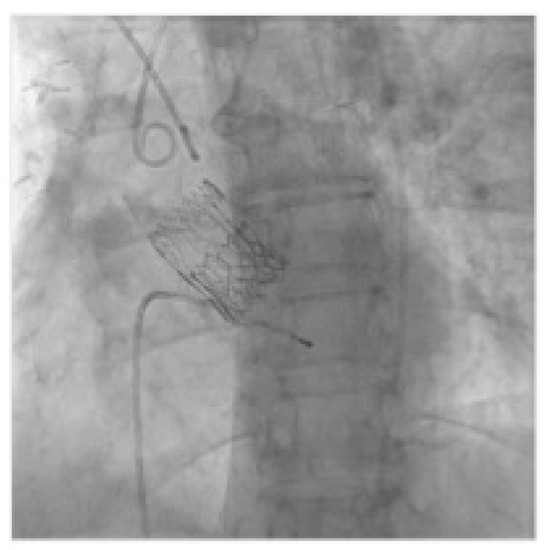

2.2. Technology

2.3. VIV-TAVR Planning and Technical Procedures